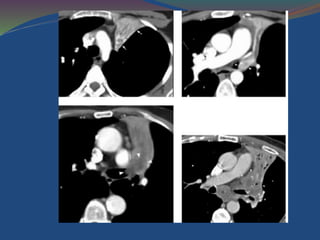

CT scan: diffusethickening of tracheal wall with abnormal calcification and narrowing of the tracheal lumen. (B) CT scan just below level of canna shows identical abnormalities extending into both main bronchi.